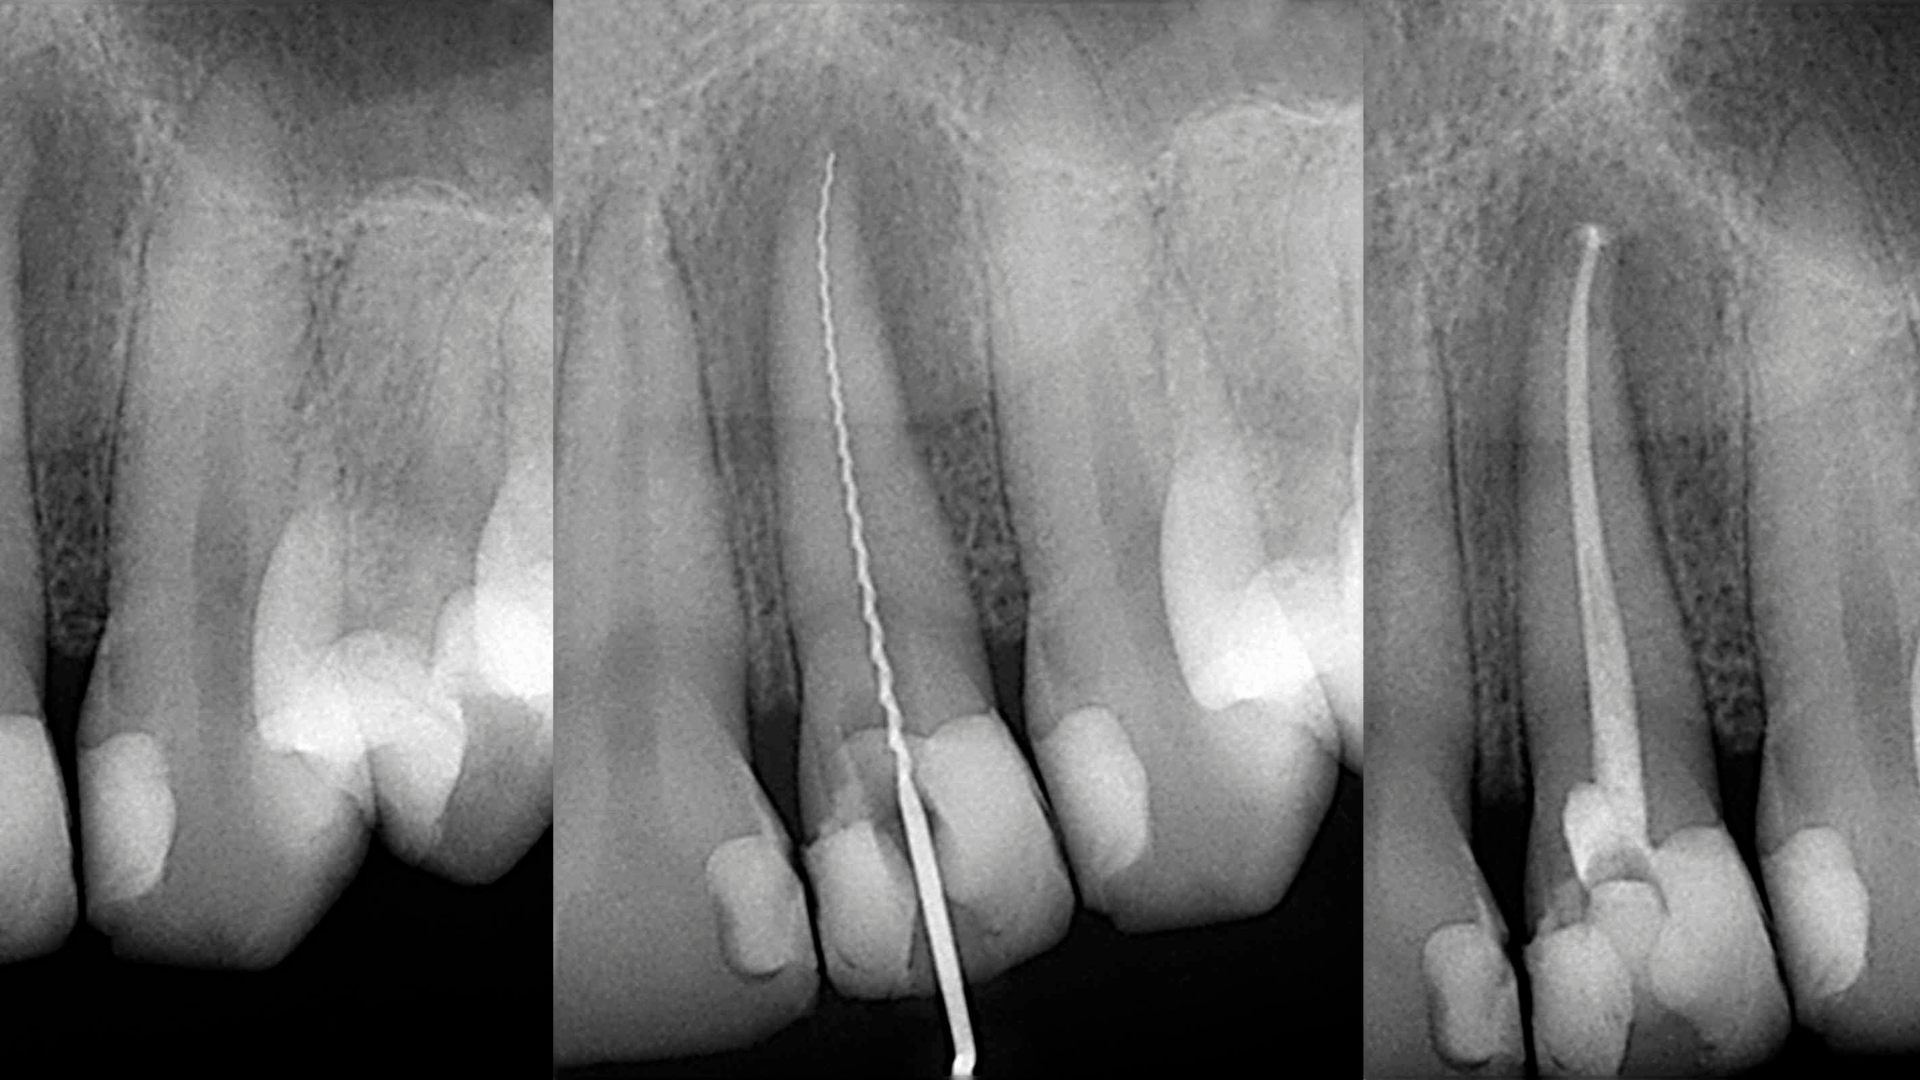

Endodoncia

La endodoncia es un tratamiento conservador indicado cuando la pulpa dental está dañada de forma irreversible y una restauración convencional ya no es suficiente. Su objetivo es eliminar el tejido afectado del interior del diente, desinfectar los conductos radiculares y permitir una reconstrucción adecuada, evitando así la extracción de la pieza.

En nuestra clínica disponemos de tecnología CBCT de alta definición, que nos permite realizar un estudio tridimensional (3D) del diente y abordar el tratamiento del conducto con mayor precisión que con una radiografía convencional.

» ¿En qué consiste un tratamiento de endodoncia?

Un tratamiento de endodoncia, comúnmente conocido como «tratamiento de conducto», consiste en eliminar la pulpa dental dañada o infectada del interior del diente (nervio), limpiar y desinfectar los conductos radiculares, y luego sellarlos para evitar nuevas infecciones. Se realiza cuando la pulpa está afectada por caries profundas, traumatismos, fisuras o infecciones. El objetivo es conservar el diente natural, aliviando el dolor y evitando su extracción. Tras la endodoncia, el diente puede necesitar una reconstrucción o una corona para devolverle su funcionalidad y resistencia. Es un tratamiento seguro, eficaz y conservador que permite mantener la pieza dental en boca.